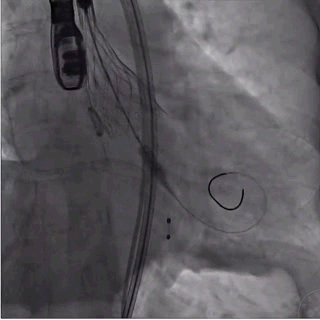

2、导丝顺利跨瓣后,在无冠窦猪尾指示下,将装载瓣膜的输送系统送至窦底;

瓣膜输送并跨瓣(过弓中)